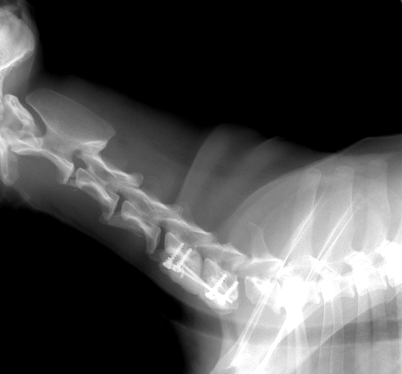

腰仙椎固定術(不安定症・脱臼・骨折)

L7 骨折